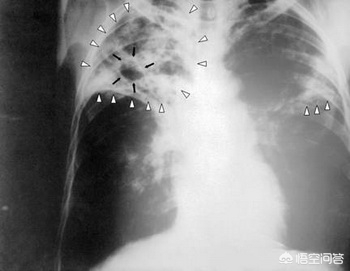

肺结核是一种重要的传染病,由于其破坏性大,传染性强,疗程长,后遗症多,发病基数大而在中国备受重视,中国是结核大国,结核患者之众在全球只有印度能与我国一争雌雄,每年结核的新发人数和患病人数都超过百万级,患病之后的痛苦令人煎熬,因此,担心感染结核是人之常情,但结核的感染也有规律可循,在结核患者得到有效治疗后基本上可以放心,复查一些项目后如果一切良好就很少有传染性了。下面介绍一下肺结核传染性方面的知识和常规注意事项。

一般来说,如果抗结核治疗效果比较好,在治疗的第一个月,结核的传染性可以下降80%-90%,但这个比例并不代表已经没有传染性,家人和周围的人仍然需要注意排除被传染的可能性,不可以过分的亲密接触,一般连续三个月反复查痰查不到结核菌的话,说明传染性就很小了,然而这个阶段还是不能完全放心,只要患者有痰排出来,仍需要特别注意,之所以需要注意这么久的时间和结核菌的特点有关的,结核菌生长缓慢,但杀灭起来也非常难,即使疗效很好的情况下也需要6-9个月的不间断治疗才能完全杀灭,因此,完成总疗程后没有任何不适,就可以完全排除传染性了。

因此,肺结核在完成治疗后,复查胸部CT已经痊愈的情况下,是没有传染性的,但是需要预防复发的情况,复发后存在一定的传染性。